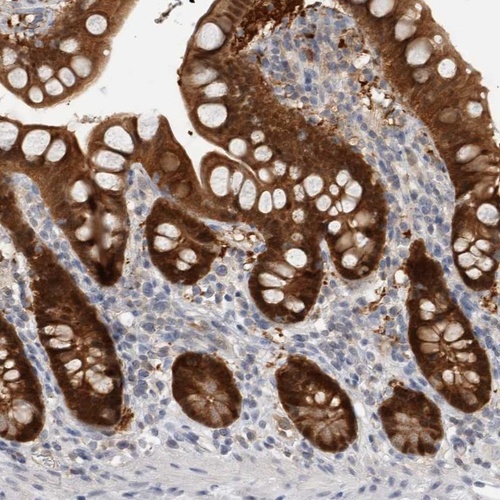

Immunohistochemistry analysis in human small intestine and skeletal muscle tissues using Anti-CASP6 antibody. Corresponding CASP6 RNA-seq data are presented for the same tissues.